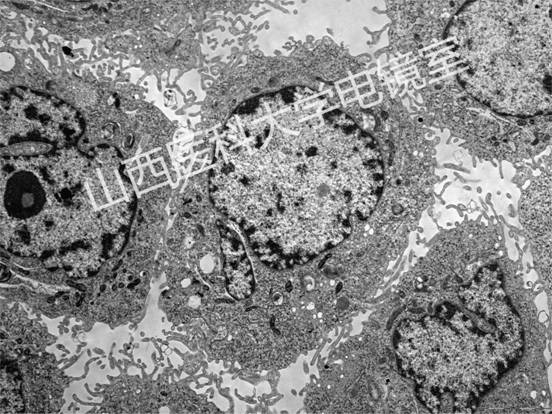

代表性圖譜:

心肌